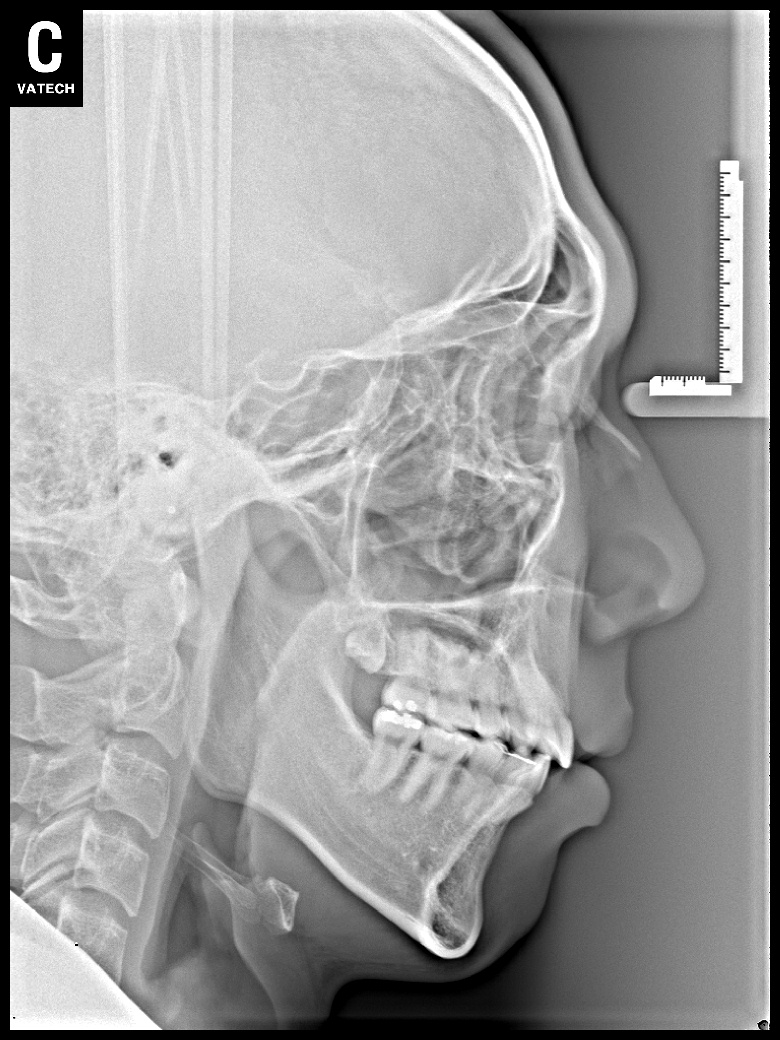

치료 후 사진입니다.